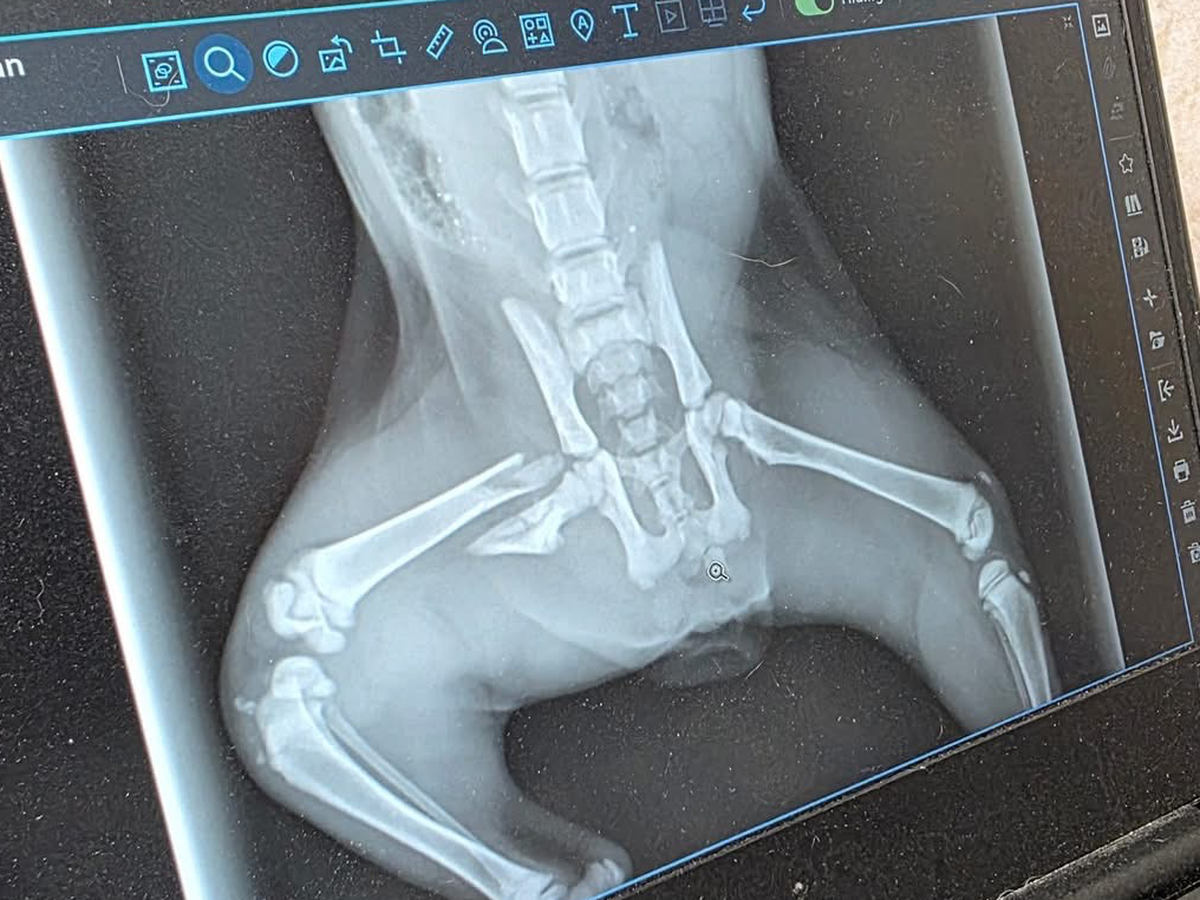

We were driving down 61st and Lewis when Ryan stopped in traffic to save this kitty. She was laying in the middle of the road, unable to move. We rushed her to the vet and found out she has a broken leg that will need to be amputated.

As most of you know, we love to rescue, and we will be taking this kitty home to give her a good life. We’re putting this out here to see if anyone could help contribute to her surgery she will be having Monday. Thank you for reading.